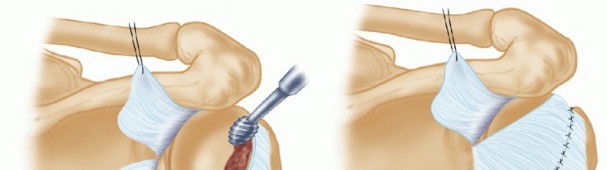

Repair is begun by assessing the posterior labral construct for the presence of labral displacement and tearing (TECH FIG 1A).

If a posterior Bankart lesion is identified, a Liberator knife (ConMed Linvatec) is used to mobilize the labrum (TECH FIG 1B), and a burr is used to débride the posterior face of the glenoid in preparation for anchor placement (TECH FIG 1C).

This is a critical step so that a freely mobile labrum can be placed up on the glenoid, thereby restoring its bumper effect. Anchor placement begins at the most inferior aspect of the glenoid, usually the 5:30 or 6:30 position, depending on the side involved (TECH FIG 1D).

TECH FIG 1 • A. Probe entering the posterior cannula is demonstrating mobility of posterior Bankart lesion with evidence of granulation tissue in the defect. B. After the lesion is defined, a Liberator knife is introduced to take down the fibrous interface in the posterior Bankart lesion. C. After preparation using a high-speed burr, the posterior inferior aspect of the glenoid is lightly decorticated in preparation for anchor placement. D. Initial anchor placement begins at the inferior extent of the glenoid with the use of a guide. E. First anchor in place 2 mm up on the articular surface.

This position allows secure placement of an anchor while allowing optimal inferior capsular plication. Bioabsorbable anchors are employed for this reconstruction (TECH FIG 1E).